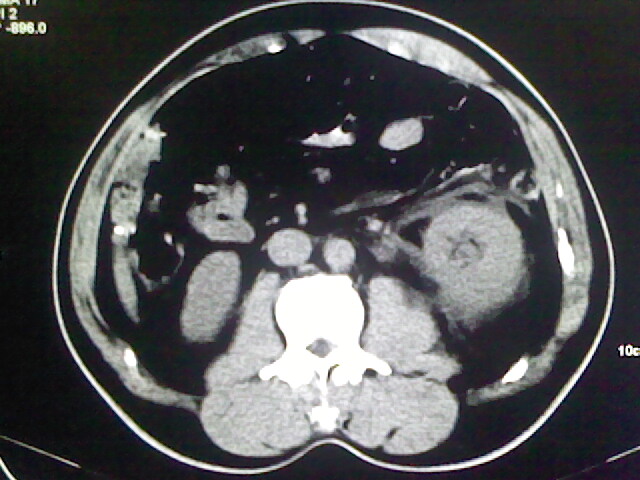

以下是引用zsl6918在2009-2-7 7:29:00的发言:[br]请提供介入的方式方法,肾及输尿管改变考虑与介入损伤有关,漏了,尿液外渗。

以下是引用余辉在2009-2-7 8:27:00的发言:[br]可能是硬化剂烧穿囊壁进入肾盂输尿管了,尿漏。不除外介入或碎石术后合并感染[br]患者术后怀疑结石,接着就碎石了?就怀疑没有确诊吗?碎石用的什么方法?气压弹道还是体外超声?如果这样的话责任人都难找

以下是引用随光逐影在2009-2-7 8:46:00的发言:[br]支持3楼意见。[br]另:不排除左肾及肾周感染可能。